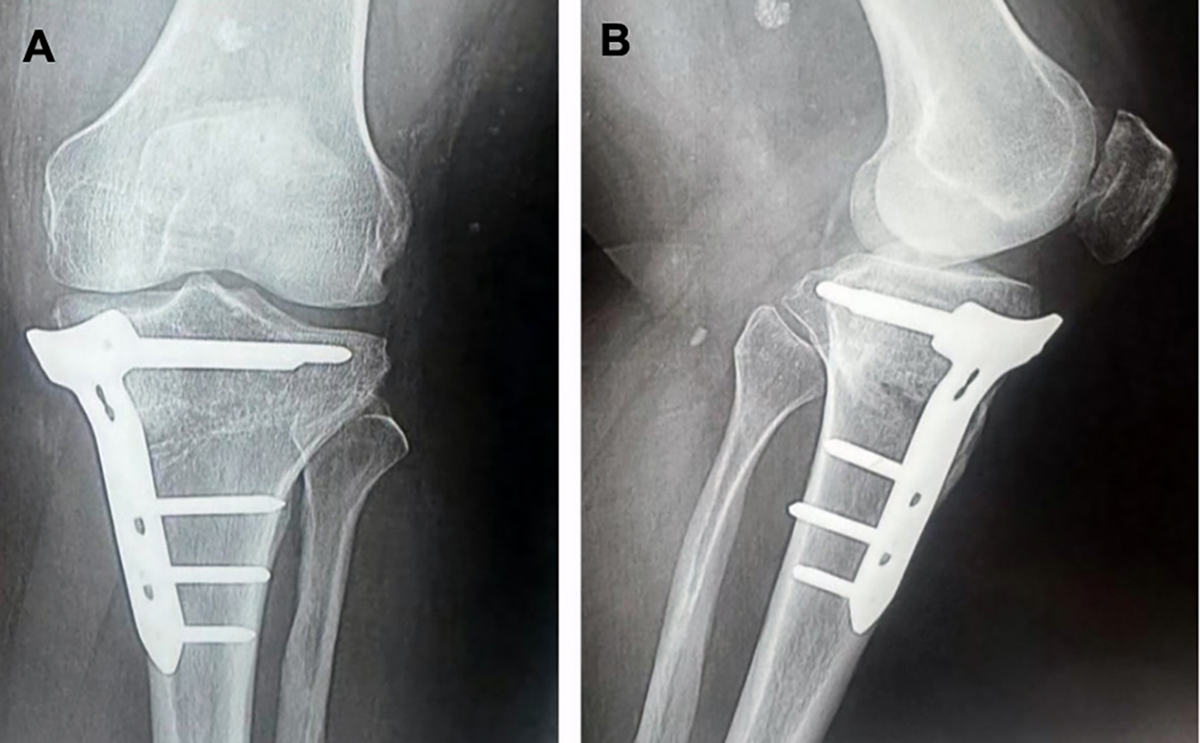

A 6-week postoperative knee X-ray (A) anteroposterior and (B) lateral views, showing healing of osteotomy site.